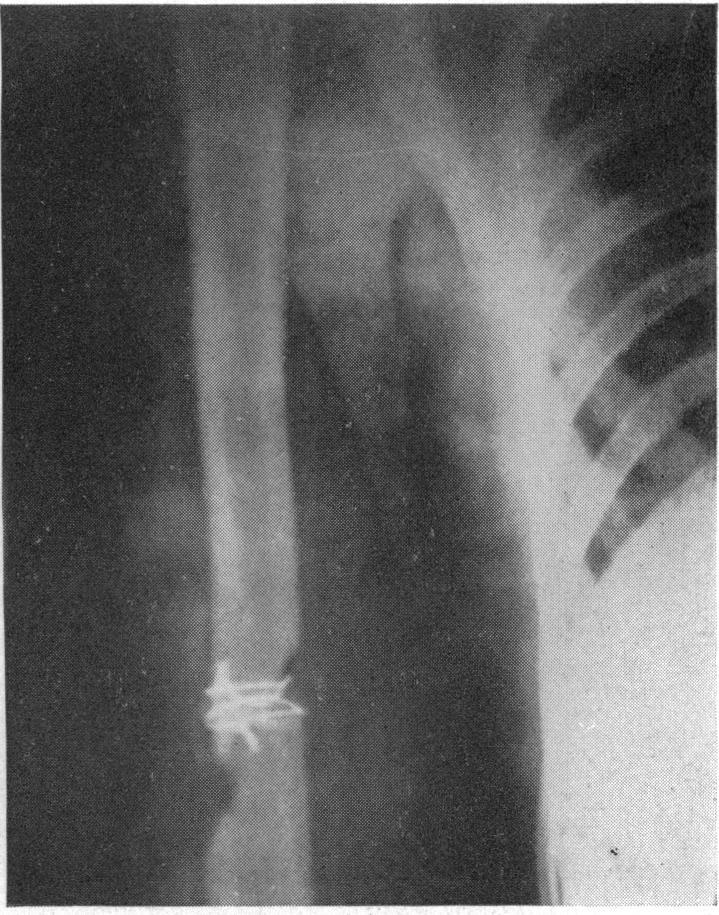

6

[Aseptic non-union of humeral shaft fractures treated by plating and bone grafting. Report of 20 cases].

Chir Main. 2013 Apr;32(2):85-91. doi: 10.1016/j.main.2013.02.003. Epub 2013 Feb 28.